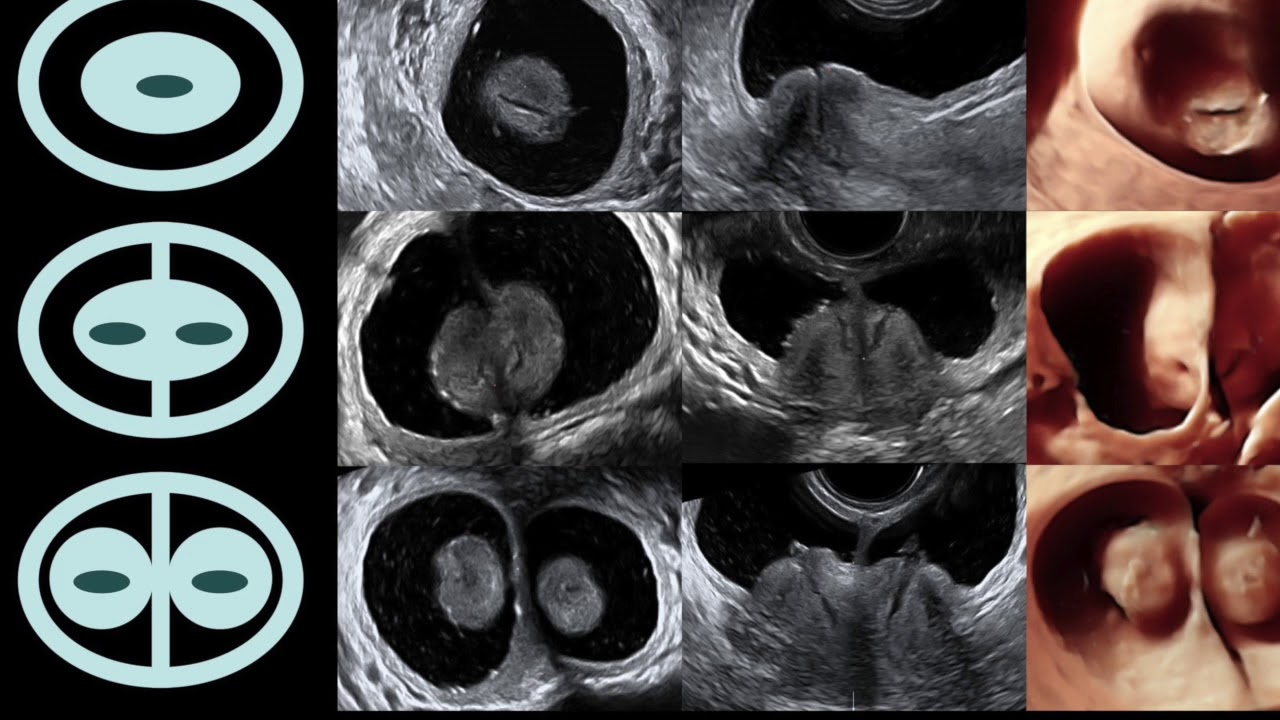

Autor własnej histeroskopowej techniki usuwania mięśniaków podśluzówkowych i śródściennych macicy z wykorzystaniem transrektalnej ultrasonografii śródoperacyjnej, umożliwiającej małoinwazyjne leczenie bez konieczności otwierania powłok brzusznych czy rozcinania macicy (Opis opublikowany przez prestiżowy amerykański Journal of Minimally Invasive Gynecology.

Tytuł doktora nauk medycznych uzyskał na podstawie obronionej z wyróżnieniem rozprawy doktorskiej z tego zakresu pt. „Transrektalna ultrasonografia śródoperacyjna w monitorowaniu histeroskopowej elektroresekcji mięśniaków podśluzówkowych macicy”.